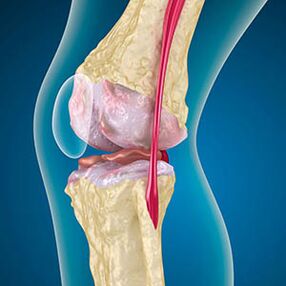

Bei Osteoarthritis ist der Knorpel, der die Knochenkanten abdeckt, Abrieb oder vollständig fehlend. Beschädigter Gewebe ist keine Schmerzquelle, da es keine Empfänger hat. Entzündungen in nahe gelegenen Strukturen verursachen charakteristische Symptome.

Der Körper setzt die Regeneration von beschädigten Geweben fort, aber der Knorpel wächst ungleich. Infolgedessen bilden sich Unregelmäßigkeiten, die andere Elemente der Artikulation beschädigen. Die Art der Osteophyten wird durch Entschädigung für den Knorpel der glatten Gelenke erklärt. Eine andere Version zeigt, dass das Wachstum von "Spurs"Es ist mit dem Versuch verbunden, das mediale oder laterale Gelenk aufgrund einer Muskelschwächung zu stabilisieren.

Die Schwellung wird durch eine Weichteilverletzung, eine Entzündung der Sehnen und die Gelenkbeutel verursacht. Das Erscheinungsbild von Wärme im Knie zeigt die Ansammlung von entzündlichen Exsudat an -Arthrose wird häufig von Bursitis, Synoviten und Sehnenentzündungen begleitet.